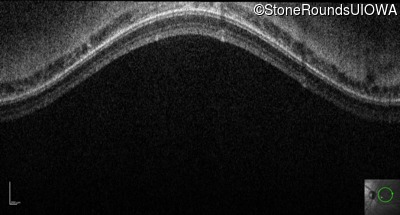

Optical Coherence Tomography - Right - 10/160 +1 sc

Exemplar / OCT Stack